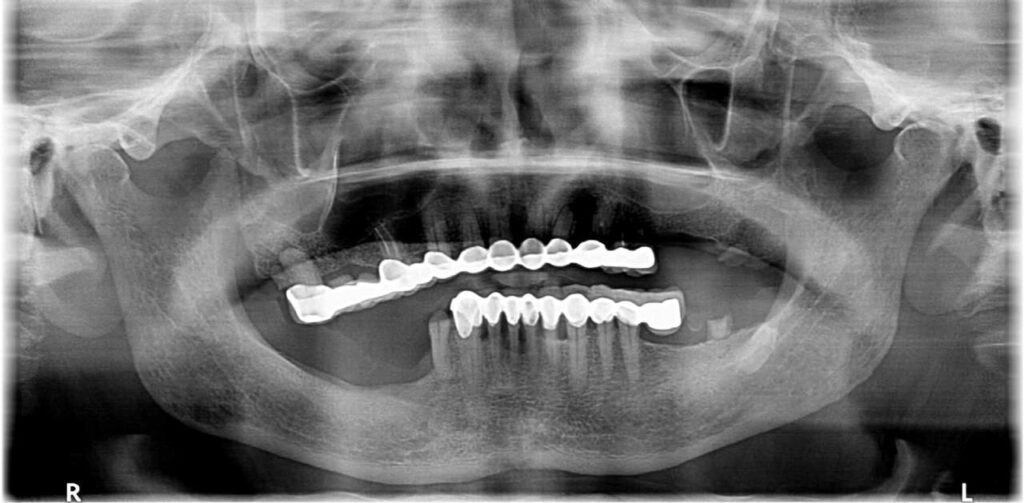

سجّل مستشفى الأسنان بمدينة الملك سعود الطبية، عضو تجمع الرياض الصحي الأول، خطوة طبية نوعية تمكّن خلالها فريق طبي متعدد التخصصات من تنفيذ حالة دقيقة ومعقدة، تضمنت خلع جميع الأسنان المتضررة لدى أحد المرضى وزراعتها فوريًا في الفكين العلوي والسفلي، مع تركيب تعويض تجميلي مؤقت في الجلسة نفسها.

وأوضح قائد الفريق الطبي، استشاري زراعة الأسنان الدكتور فالح الهجهوج، أن الحالة نُفذت باستخدام أحدث ما توصلت إليه تقنيات طب الأسنان الرقمي، بدءًا من استخدام جهاز الماسح الفموي الرقمي لأخذ المقاسات، وصولًا إلى تصميم وطباعة التركيبة النهائية المصنوعة من مادة الزركونيا عبر تقنيات الطباعة ثلاثية الأبعاد المتقدمة؛ مما مكّن من تقديم علاج عالي الدقة بأقل تدخل جراحي وفي وقت قياسي.

وأضاف الهجهوج أن العلاج تم على مراحل متكاملة جمعت بين التخدير، وجراحة الوجه والفكين، وزراعة الأسنان، وتعويضات الأسنان، وإخصائيي تقنية معامل الأسنان موضحًا أن هذا التكامل بين الأقسام يعكس مدى الجاهزية والاحترافية التي تتمتع بها الفرق الطبية في المستشفى، ومؤكدًا أن هذه الخطوة تعكس التزام مدينة الملك سعود الطبية بتقديم رعاية صحية متقدمة تواكب أعلى المعايير العالمية.